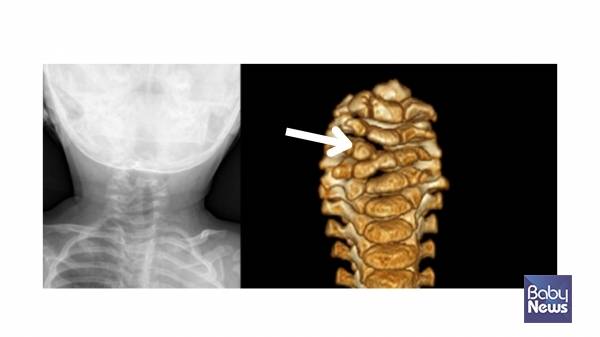

사경 아동의 약 절반은 '근성사경'입니다. 근성사경은 흉쇄유돌근이라는 목 근육이 손상되면서 짧아지고 딱딱해지는 질환입니다. 신생아의 한쪽 목에서 멍울이 만져지는 경우 가장 흔한 원인이기도 합니다.

중요한 점은, 목에 멍울이 있다고 모두 근성사경은 아니라는 사실입니다. 염증이나 종양 등 다른 질환과 감별이 필요하며, 이를 위해 가장 기본적이고 중요한 검사가 바로 '초음파 검사'입니다. 손으로 만져보거나 눈으로 보는 것만으로는 정확한 진단이 어렵습니다.

근성사경에서는 초음파 검사에서 정상 근육보다 밝게 보이는 섬유화 조직이 관찰됩니다. 이는 손상된 근육이 회복 과정에서 딱딱하게 변한 흔적입니다. 경우에 따라 MRI 검사가 도움이 되기도 하는데, 특히 수술 여부를 판단해야 할 때 근육 내 섬유화 정도를 평가하는 데 유용합니다.